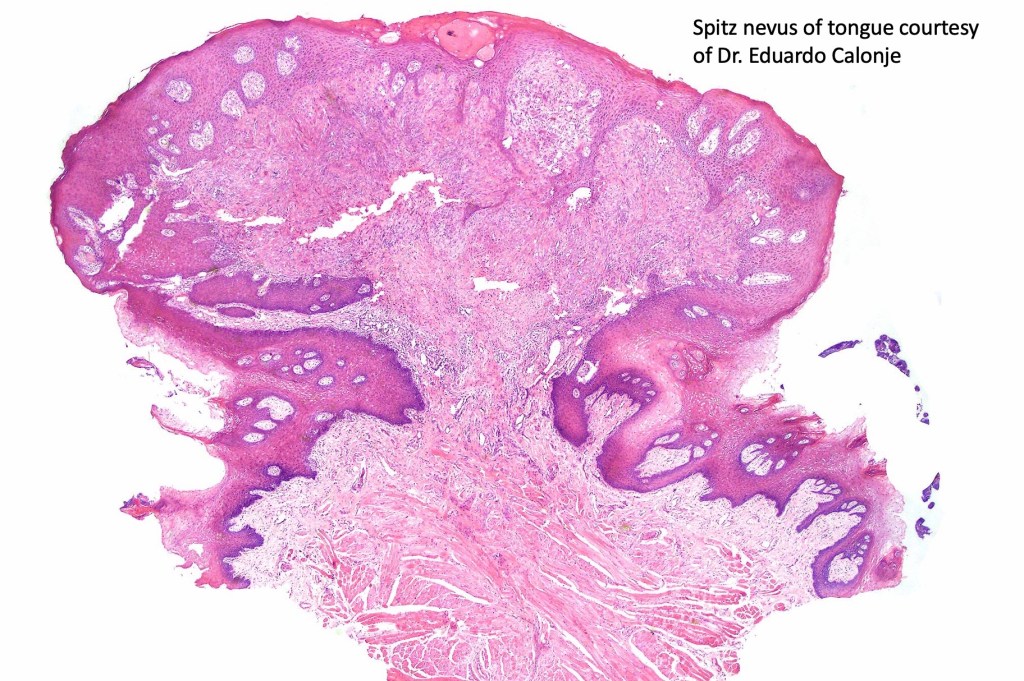

•Sharply circumscribed (begins and ends with a nest), symmetrical dome-shaped lesion. Symmetry is both horizontal and vertical (see image below)

•Wedge-shaped with the base uppermost or sometimes plaque-shaped silhouette

•Hyperkeratosis & acanthosis, sometimes very marked

•Pseudoepitheliomatous hyperplasia

•Superficial vascular ectasia very frequently present

•Lymphocytic infiltration at the base of the lesion